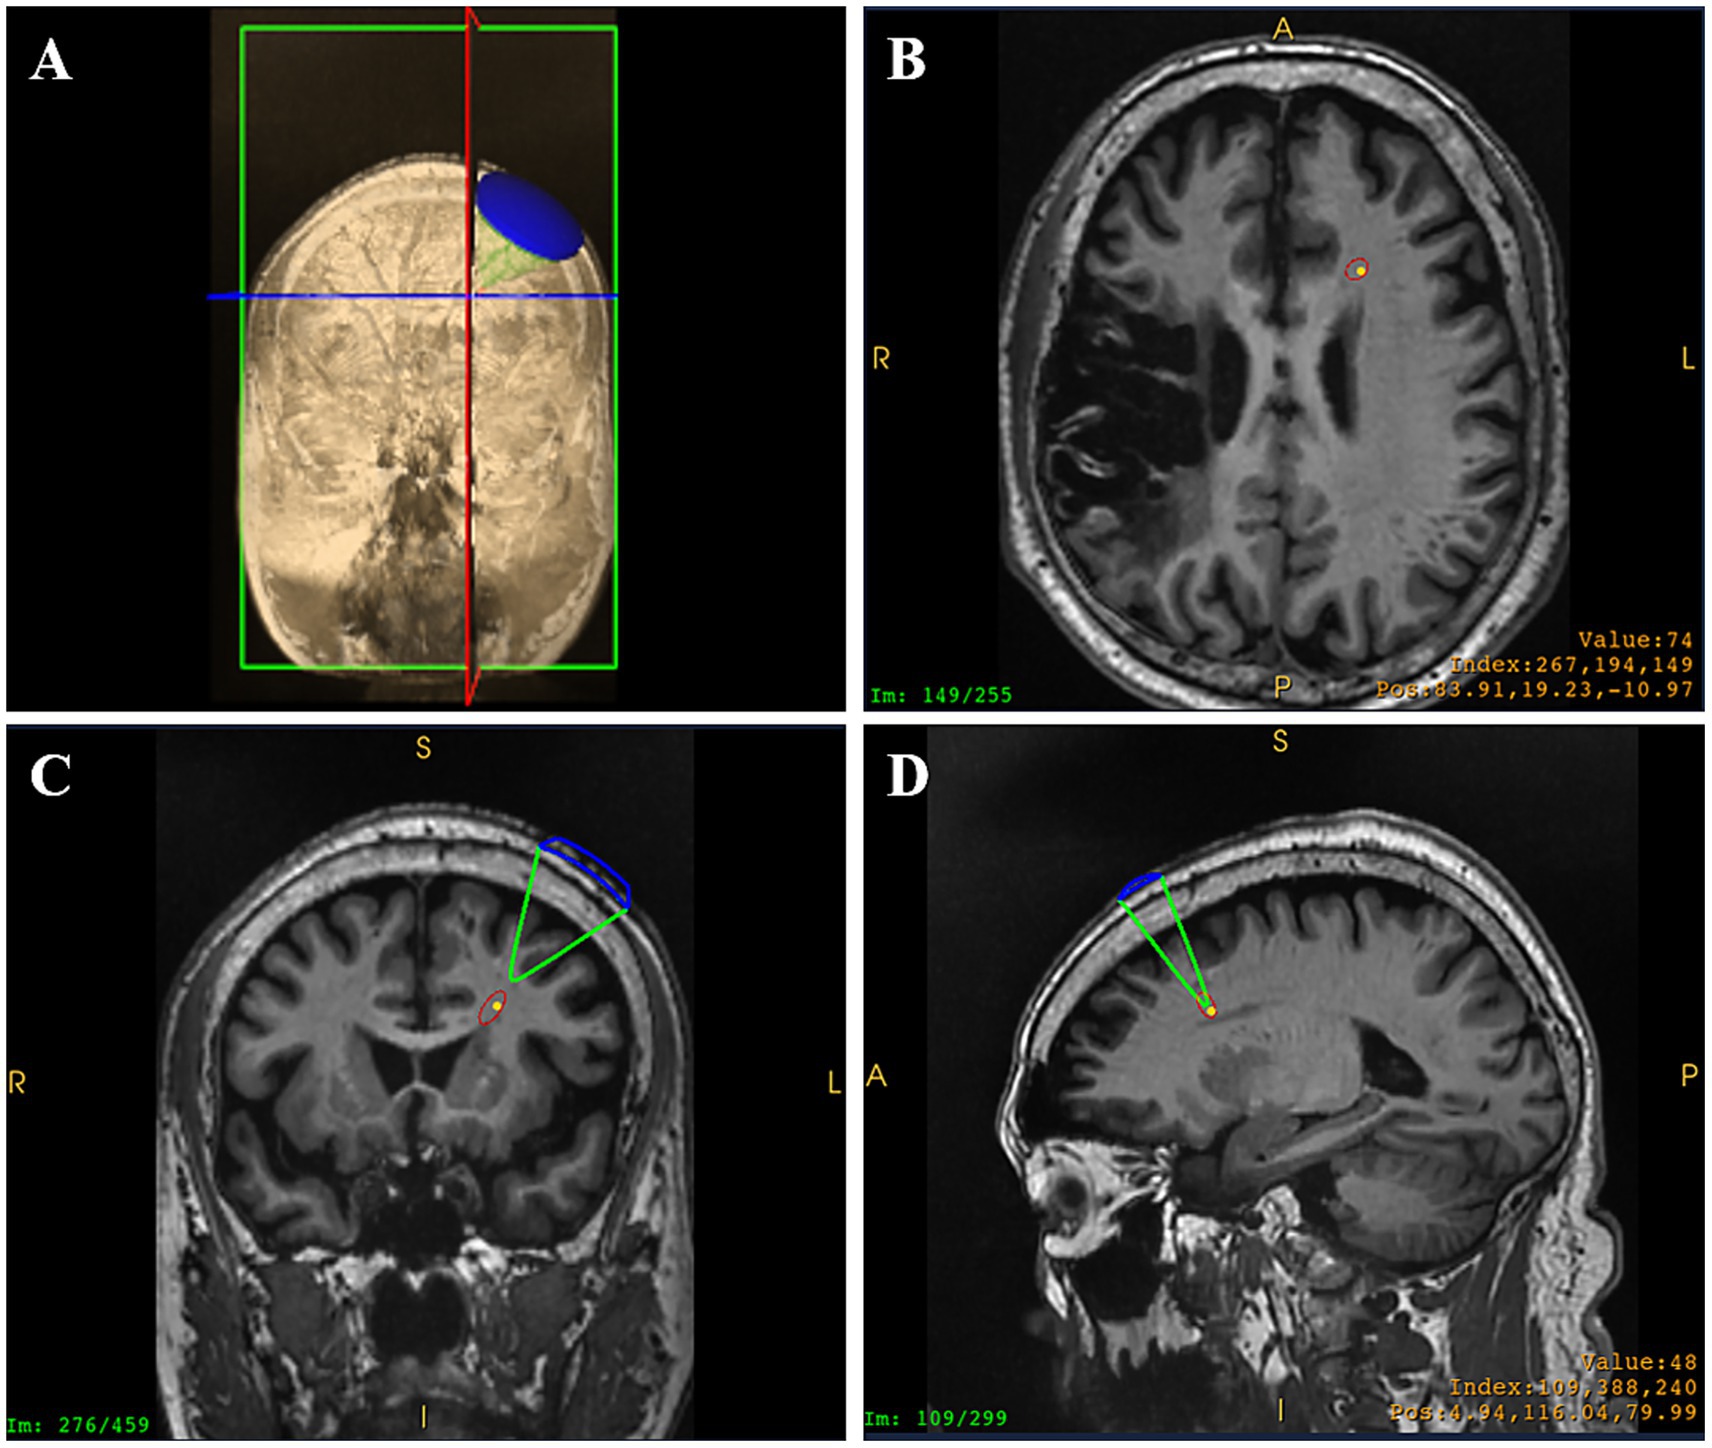

On 31 December (day 1) 2024, blood biochemistry, neuroelectrophysiological, and pain scale assessments were performed (treatment protocol, see Figure 1). On 1 January 2025, when the patient’s CPSP reached a VAS score of 6, BOLD-fMRI revealed two areas of abnormal signal in the patient’s left cerebral hemisphere: region of interest 1 (ROI1) and region of interest 2 (ROI2). From January 2 to 5, ibuprofen sustained-release tablets 0.3 g twice daily were added as an analgesic adjustment for pain relief. Subsequent cranial BOLD-fMRI showed resolution of the abnormal signals in both ROI1 and ROI2 (see Figure 2). In view of (1) the changes in BOLD-fMRI resulting from painkiller adjustment, (2) our prior animal study demonstrating that tLIFU modulation of the anterior cingulate cortex (ACC) effectively alleviated chronic neuropathic pain in mice (Feng et al., 2021), and (3) the proximity of ROI1 to the ACC on the healthy side (the left ACC), ROI1 was therefore selected as the target for tLIFU treatment in this patient. From January 5 to 18, 2025, gabapentin 0.3 g three times daily was prescribed for pain management without using other analgesics. During this period, the patient’s VAS scores fluctuated between 4 and 6, with daily pain attack frequency of 7–8 episodes, each lasting 30 min to 1 h. To preclude interference effects, no other neuromodulation techniques besides tLIFU have been administered to this patient since November 2024. The first neuromodulation via the tLIFU system (GreenValley BrainTech Medical Technology Corporation) with a single-element focused ultrasonic transducer (F0050A03) was carried out on January 18, 2025 (schematic diagram, see Figure 3). The surface of the transducer is circular, with a focal length of 46.8 mm and a focal spot size of 4.80 mm * 4.70 mm * 38.29 mm. The depth of the focal point can be adjusted by modifying the collimator attached to the transducer. To minimize the impact of the thickness of the human skull, the range of tLIFU fundamental frequency that is often used is 250–650 kHz (Cox et al., 2025). A study from our team indicated that tLIFU stimulation with acoustic pressure below 2 MPa is safe for C57 mice (Wang et al., 2022) and that tLIFU stimulation with a duty cycle (DC) of 1.6%, a spatial-peak time-average intensity (ISPTA) of 113.47 mw/cm2, and a spatial-peak pulse-average intensity (ISPPA) of 28.37 w/cm2 improved social interaction and stereotyped behavior in a boy with autism spectrum disorder (Cheng et al., 2025). Therefore, tLIFU parameters in this study were as follows: the fundamental frequency was 0.5 MHz, the peak-to-peak acoustic pressure was 0.83 MPa, the ISPTA was 53.73 mW/cm2, the ISPPA was 5.37 mW/cm2, the pulse repetition frequency (PRF) was 200 Hz, and the DC was 1%. The therapeutic session lasted 20 min and was administered once daily for 7 consecutive days. Within the duration of tLIFU therapy, the transducer was placed properly relative to the skull, and its focus of the transducer was aligned with the target site and monitored in real-time to achieve precise neuromodulation (Figure 4). The final tLIFU intervention was completed on 24 January 2025, by which time the dose of gabapentin was tapered to 0.3 g twice daily, with no concomitant use of other analgesics or topical analgesic patches. Clinical assessments demonstrated significant reductions in pain, anxiety, and depression symptoms (see Table 1). Electromyography (EMG) revealed normalized motor conduction in the left tibial nerve and restored sensory conduction in the left ulnar nerve. The immediate electroencephalography (EEG) at the end of the last tLIFU treatment detected epileptiform discharges during photic stimulation (see Table 2). No treatment-emergent adverse events were observed during the therapeutic course, such as blood biochemistry abnormalities, neurological deficits, dizziness, headache, or epileptic seizures. Follow-up at 2-month post-tLIFU neuromodulation demonstrated sustained control of pain and emotional symptoms, with no significant exacerbation of limb pain during rehabilitation exercises. Gabapentin maintenance dose remained at 0.3 g twice daily, without supplementary analgesic or topical analgesic patches. No subjectively reported adverse events were documented, and the EEG showed an absence of epileptiform discharges. At 3-month follow-up, the analgesic efficacy persisted with the continued absence of patient-reported adverse events (see Tables 1, 2). At the 150-day follow-up, the patient had discontinued analgesics for 1 month, with no significant worsening observed in pain or mood (see Table 1), and BOLD-fMRI revealed no abnormal signal in ROIs (Figure 2).

Figure 4

Transducer placement (A) and real-time monitoring of tLIFU focus in the horizontal plane (B), the coronal plane (C), and the sagittal plane (D) within the therapeutic session (the yellow dot represents the preset neuromodulation target, and the red ellipse represents the focus of the ultrasound transducer. A, anterior; F, feet; H, head; I, inferior; L, left; P, posterior; R, right).